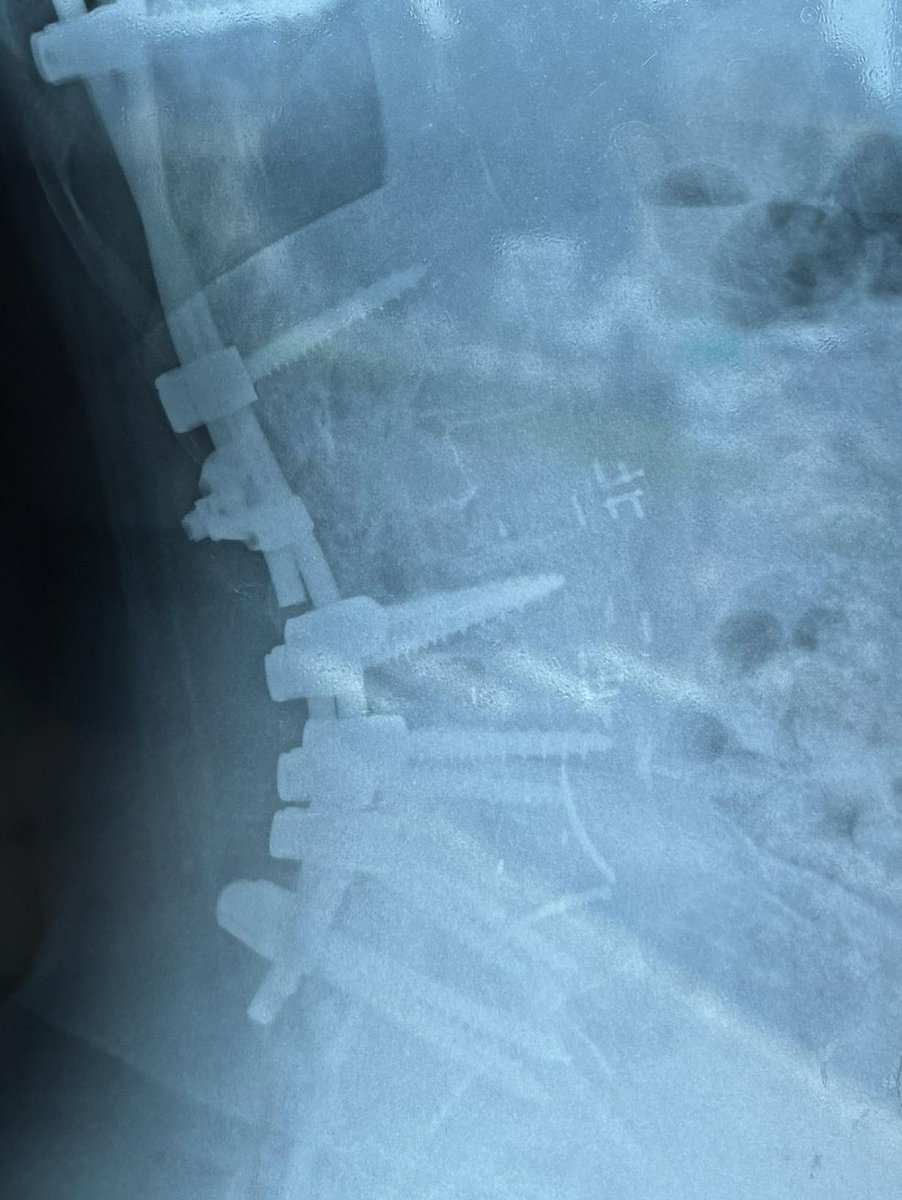

Bah voilà la poisse continue une tige de mon arthrodèse a cassée je douille au plus haut point je vis dans mon lit depuis 15 jours je vais devoir subir ma euh 10 eme operation pour cette satanée scoliose le sors s’acharne sur moi 😭 si vous avez la santé sérieux bénissez le ciel